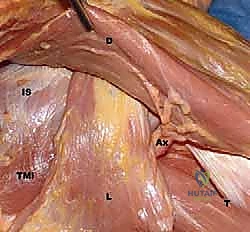

FIG 1 • A. Cadaveric dissection showing the interval between the teres major (TMa) and latissimus dorsi (L) tendons, with the radial nerve (R) deep to the latissimus and the axillary nerve (Ax) superior.

- Axillary Nerve: The axillary nerve runs superior to the latissimus dorsi tendon before exiting the quadrangular space. In neural rotation and adduction, the average distance between the nerve and the superior border of the tendon is 1.9 cm. Like the radial nerve, this distance increases with external rotation and abduction and decreases with internal rotation.

FIG 1 • C. Cadaveric dissection of the superficial muscular anatomy of the posterior shoulder, showing the axillary nerve (Ax) exiting the quadrilateral space.

FIG 4 • B. The latissimus dorsi (L) is identified and separated from the teres major (TMa).